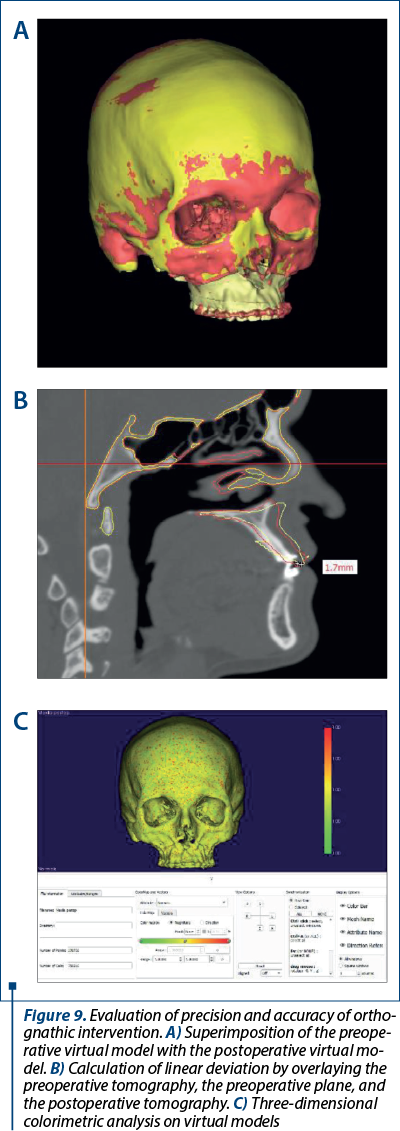

Virtual surgical planning technology is also a tool for evaluating the postoperative results obtained (Figure 9). Because this technology allows for more predictable planning of surgical treatment, it is well suited for use in craniofacial anomalies(26). In fact, recent studies have indicated that such fusion techniques can predict actual postoperative outcomes more accurately than single treatment planning approaches(24).

These studies indicate that the mean linear differences between simulation and surgical results in patients with complex craniofacial deformities were only 0.85 mm, with an angular discrepancy of only 1.7°(26). Given previous data suggesting that differences of up to 2 mm and 4° are clinically insignificant, it is clear that the analysis and manipulation of the 3D images by the software contribute to the highly predictable results in these cases(27).